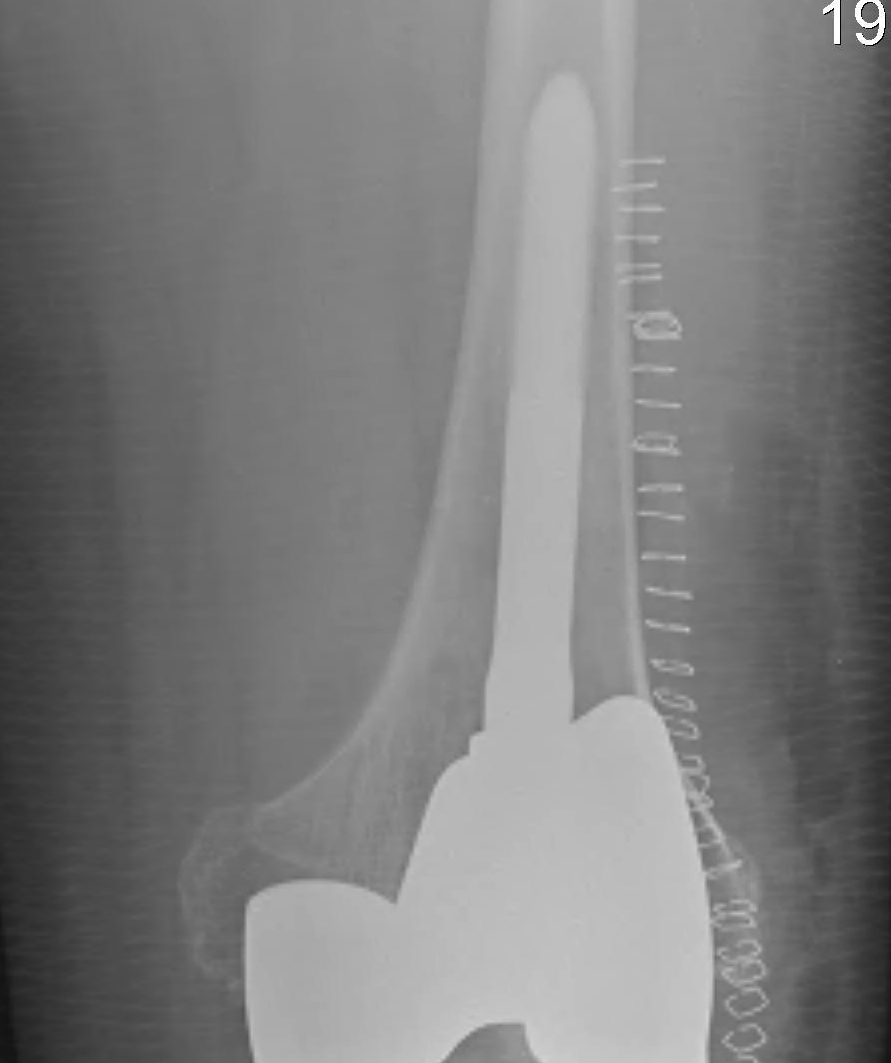

Types

Uncemented

Cemented

Press fit uncemented

Design

- cemented in metaphysis and condyles

- uncemented in diaphysis

- need to engage diaphysis

- often need offest options from tibial tray

- this is so can implant stem in correct position